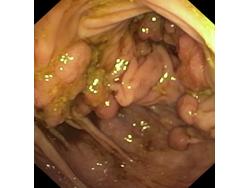

Obrazy endoskopowe

Polipowatość

Polipy

Nowotwory przewodu pokarmowego